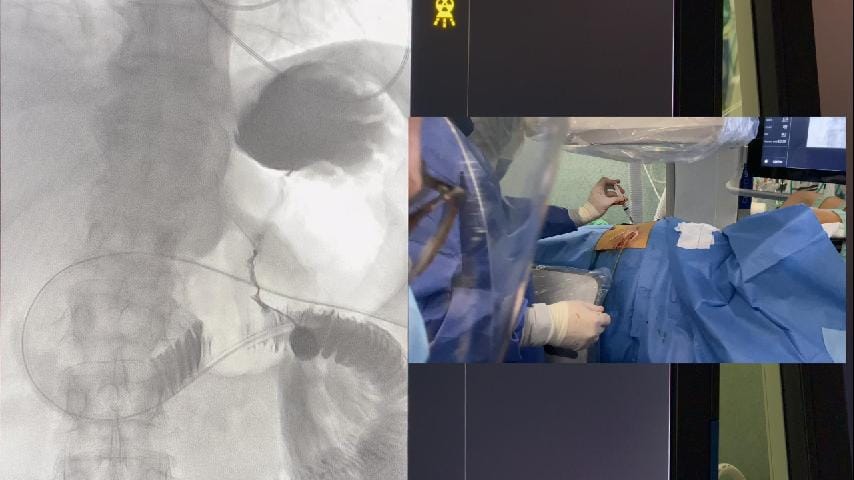

Embolización de varices pélvicas

El Dr. Andrés Guirola realiza embolización de varices pélvicas mediante cateterización de la vena gonadal.